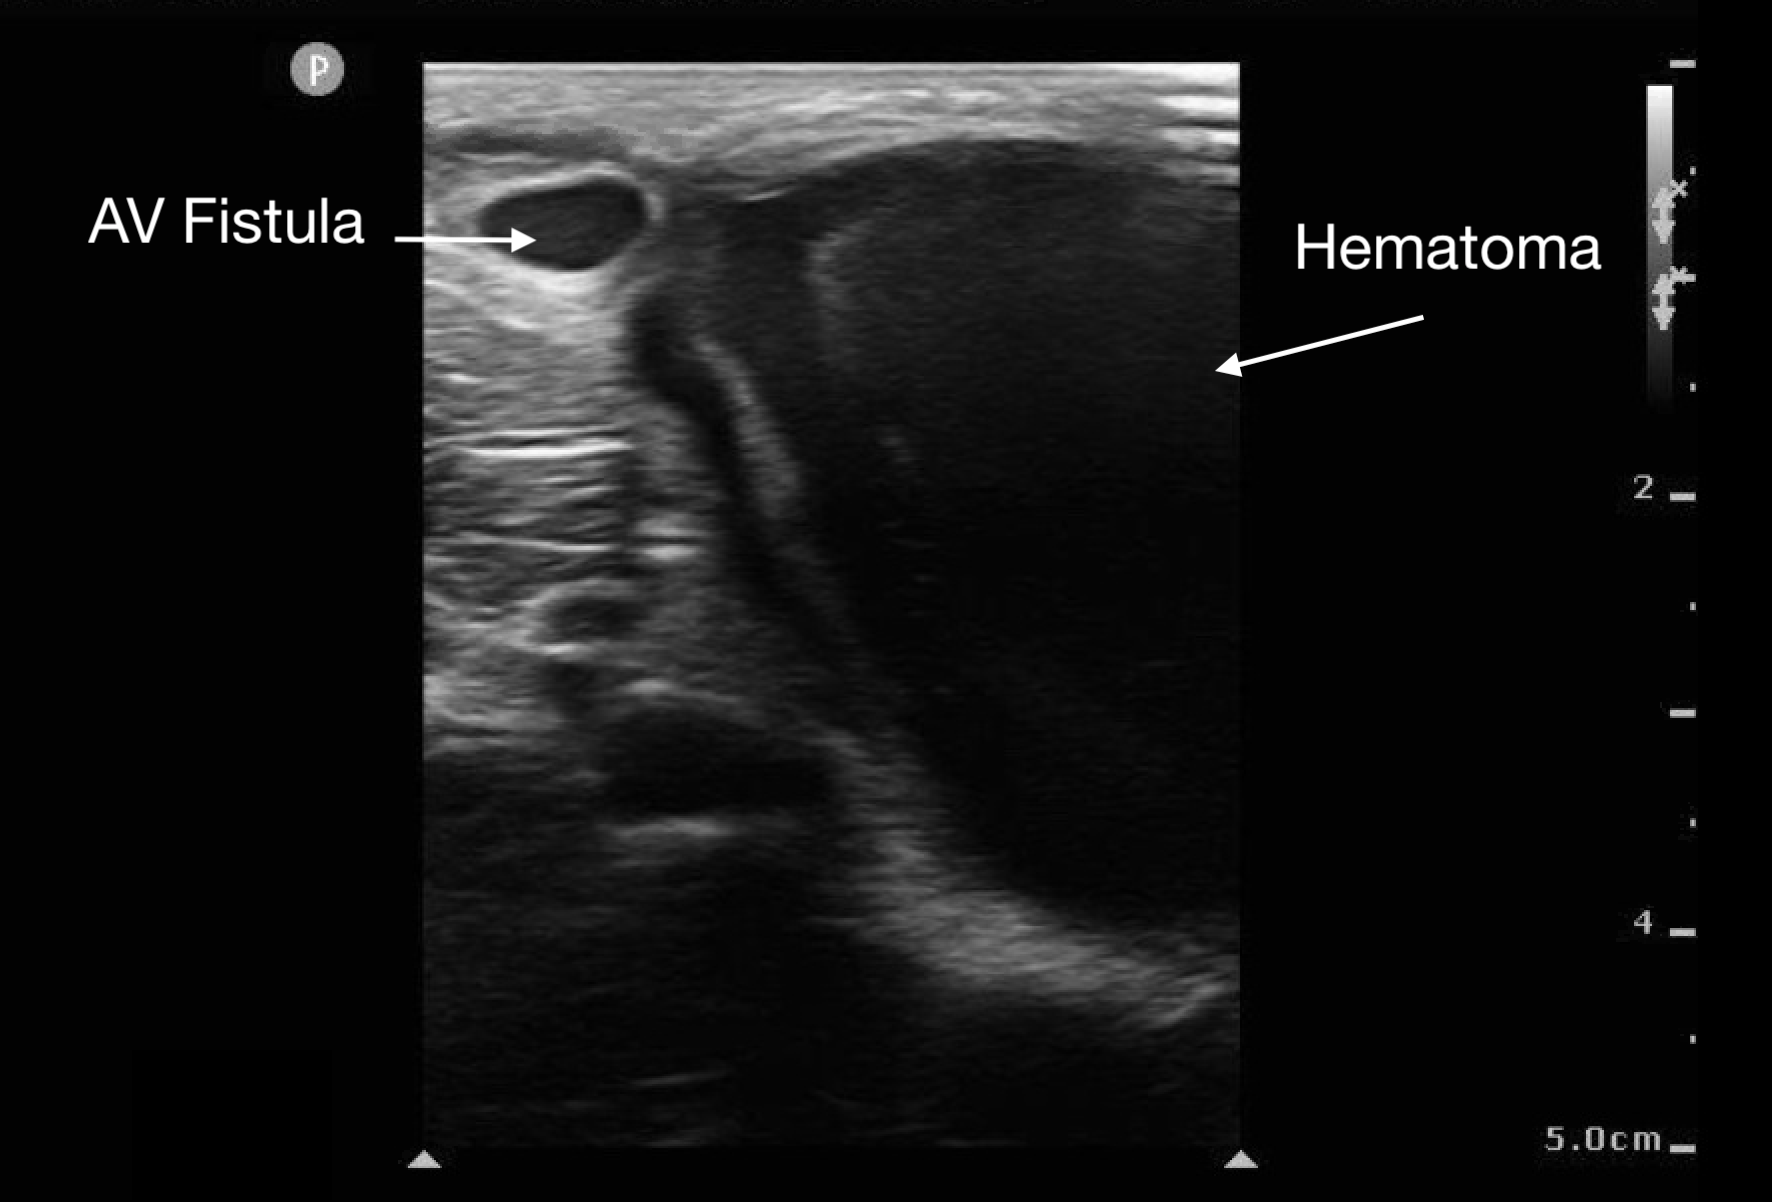

Soft Tissue

Abscesses and hematomas are readily identifiable on ultrasound as abnormal fluid collections in areas of tenderness or swelling. The appearance of the fluid varies depending on its contents, the presence of gas, and the clotting state of the hematoma. Fluid may appear anechoic (most common), heterogeneous, or even isoechoic. A key indicator in uncertain cases is the posterior acoustic enhancement generated by the fluid contents.

Figure 10.

Figure 11.

Large hematoma from ruptured AV fistula seen in upper left corner of image.

Before draining an abscess, it is crucial to use color Doppler to rule out a pseudoaneurysm or nearby large vessels. This step helps prevent inadvertent incision into a vascular soft tissue structure, such as a lymph node, which may appear similar to an abscess.